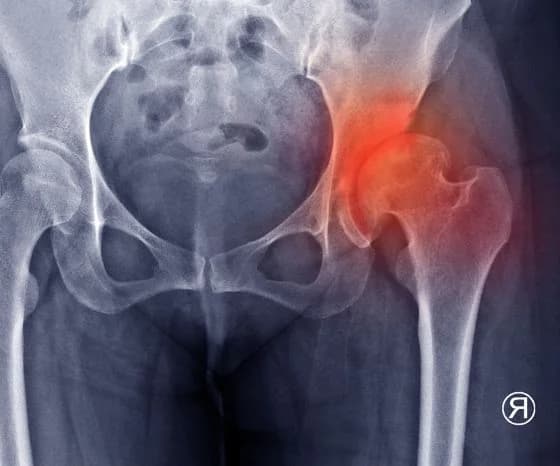

Клінічне випробування при остеоартриті кульші

У клінічному дослідженні, опублікованому в «Annals of Internal Medicine», взяли участь 120 пацієнтів з остеоартритом кульші. Учасників рандомізували до груп із різними типами взуття та рекомендували носити його щонайменше шість годин на день упродовж шести місяців.

Після завершення періоду спостереження оцінювали зміну болю під час ходьби. Пласке гнучке взуття не продемонструвало переваги над стабільним підтримувальним у зменшенні болю при остеоартриті кульші .

Автори припускають, що різниця між результатами для коліна й кульші може бути пов’язана з тим, що колінний суглоб зазнає вищого механічного навантаження під час ходьби. Відповідно, зміна характеристик взуття може мати більш помітний клінічний ефект саме при остеоартриті коліна.